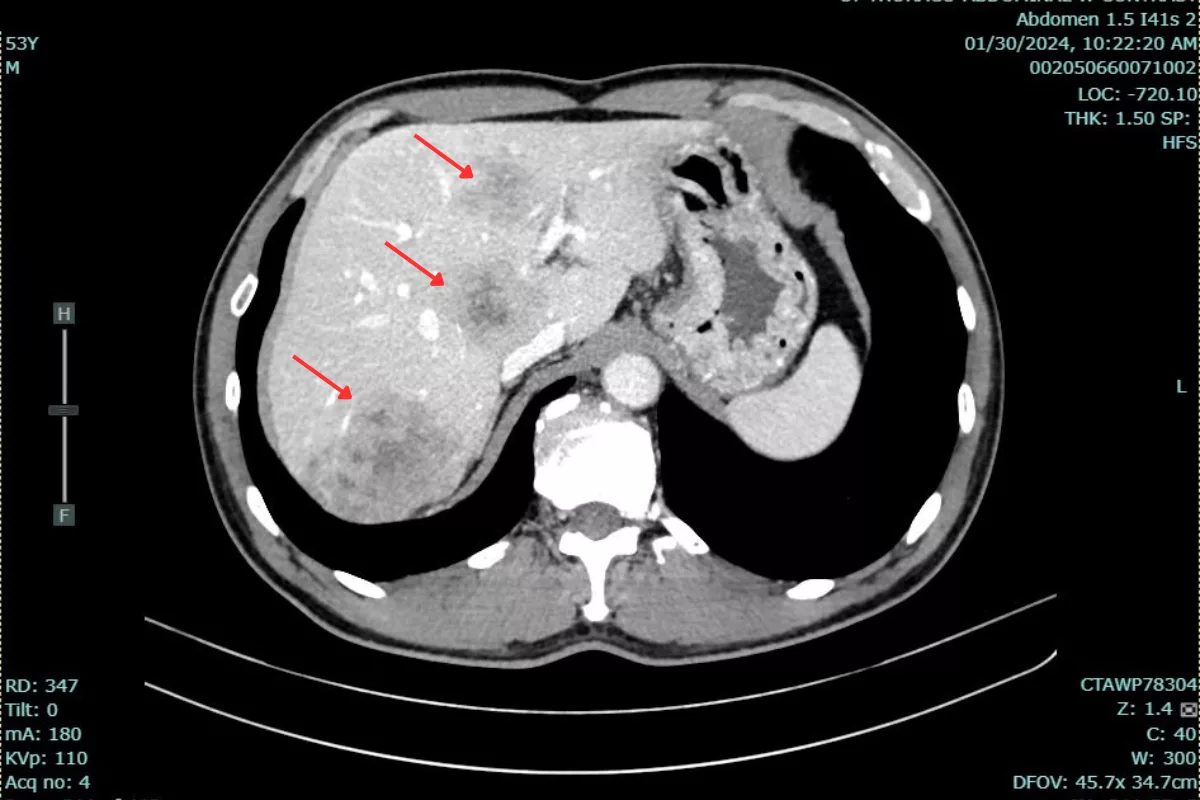

The cancer was first detected during a routine health check-up over a year ago. At that time, the patient had a large tumor located 5 cm from the anal margin, thickening of the rectal wall, and about 15 metastatic tumors in the liver, with the largest measuring 48x83x50 mm. The patient’s CEA tumor marker level was 105.6 ng/mL, significantly exceeding the normal threshold of under 5 ng/ml.

Dr. Bui Quang Loc reported:”The patient responded well to treatment. After the first cycle, some of the smaller liver lesions were no longer visible on post-treatment CT scans. After nearly a year, the largest liver lesion’s volume decreased from 78 mL to 27.26 ml. Liver metastases remained stable after treatment. Additionally, the patient’s CEA level dropped from 105.6 ng/ml to 33.6 ng/ml.”This patient’s treatment journey is a strong testament to the effectiveness of a personalized, multimodal approach in managing metastatic rectal cancer. The dedicated monitoring, tailored regimen adjustments, and close patient follow-up by the medical team at Hanoi French Hospital played a crucial role in not only controlling the disease but also improving the patient’s quality of life.